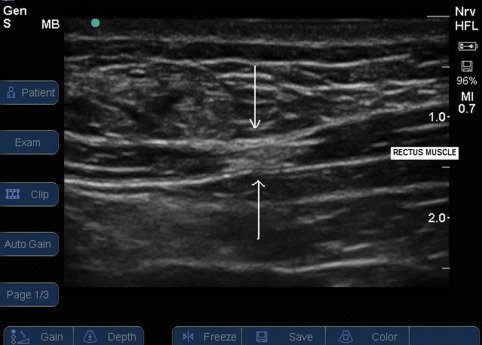

trigger img2

Trigger point visualised on Ultrasound

Early attempts to confirm the presence of myofascial trigger points using imaging, such as magnetic resonance elastography, showed promise but were not widely adopted. However, recent advancements in ultrasound have provided new hope.

Sikdar et al. have successfully utilized ultrasound to visualize and characterize trigger points. These trigger points appear as focal, hypoechoic (darker) regions with an elliptical shape, measuring approximately 0.16 cm. This breakthrough suggests that ultrasound could offer a more objective diagnosis of trigger points.

29. Trigger point visualised on Ultrasound. Image taken from https://www.bjanaesthesia.org.uk/article/S0007-0912%2817%2933096-9/fulltext